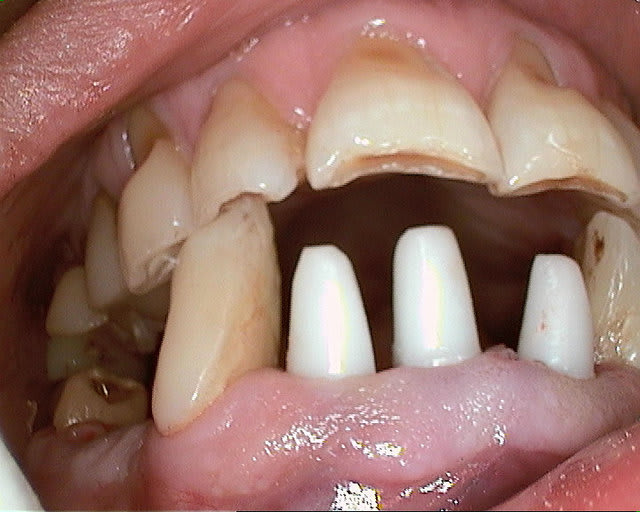

Une photo reste une photo et ne prouve rien, mais ces cas ont plus de 4 ans de recul, et ont tout les deux étés contrôlés ce mois si.

Et je le redis,ceci n'est pas une loi, c'est seulement une constatation, d'un omnipraticien qui pratique l'expansion pour planter ses clous, infiniment moins bien que Khoury... au fait duquel parles tu? Elias, Fouad ou Georges (ils sont bons, très bons même, tous les trois).

Pour vava, la procédure est classique, et à la portée de nous tous, fente de la crête, et expansion, si possible sans fracture, mais le post est sur l'épaisseur de l'os vestibulaire, pas sur l'expansion.

Ma réflexion était juste pour préciser qu'en expansion, les contraintes n'étaient pas les mêmes qu'avec un foret.